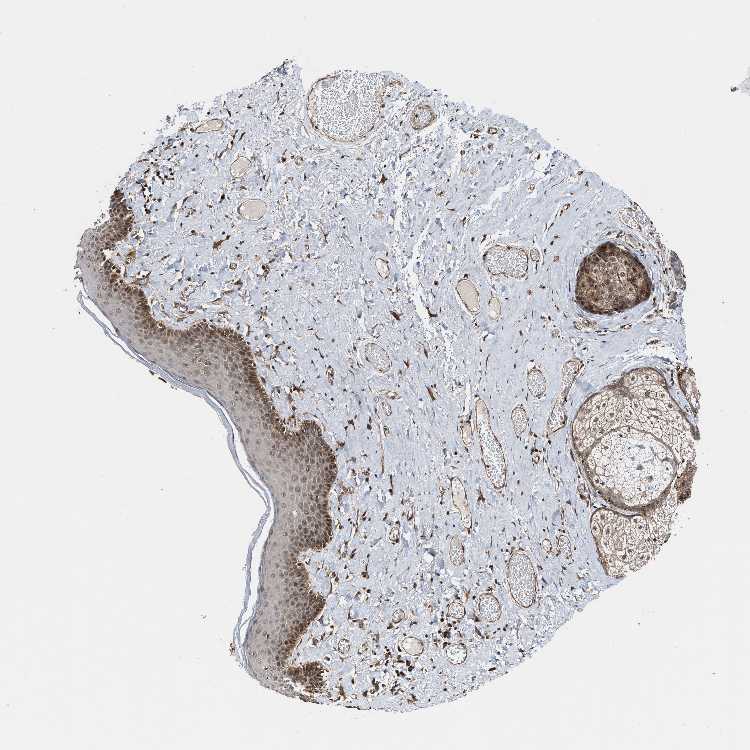

SKIN 1 - Antibody stainingi

Antibody staining in the annotated cell types in the current human tissue is reported as not detected, low, medium, or high, based on conventional immunohistochemistry profiling in selected tissues. This score is based on the combination of the staining intensity and fraction of stained cells.

Each image is clickable and will lead to virtual microscopy that enables deeper exploration of all samples and also displays staining intensity scores, fraction scores and subcellular localization as well as patient and tissue information for each sample.

Antibody HPA018481Antibody CAB017190

Langerhans Not detectedLow

Fibroblasts LowHigh

Keratinocytes LowMedium

Melanocytes LowMedium

SKIN 2 - Antibody stainingi

Epidermal cells MediumHigh